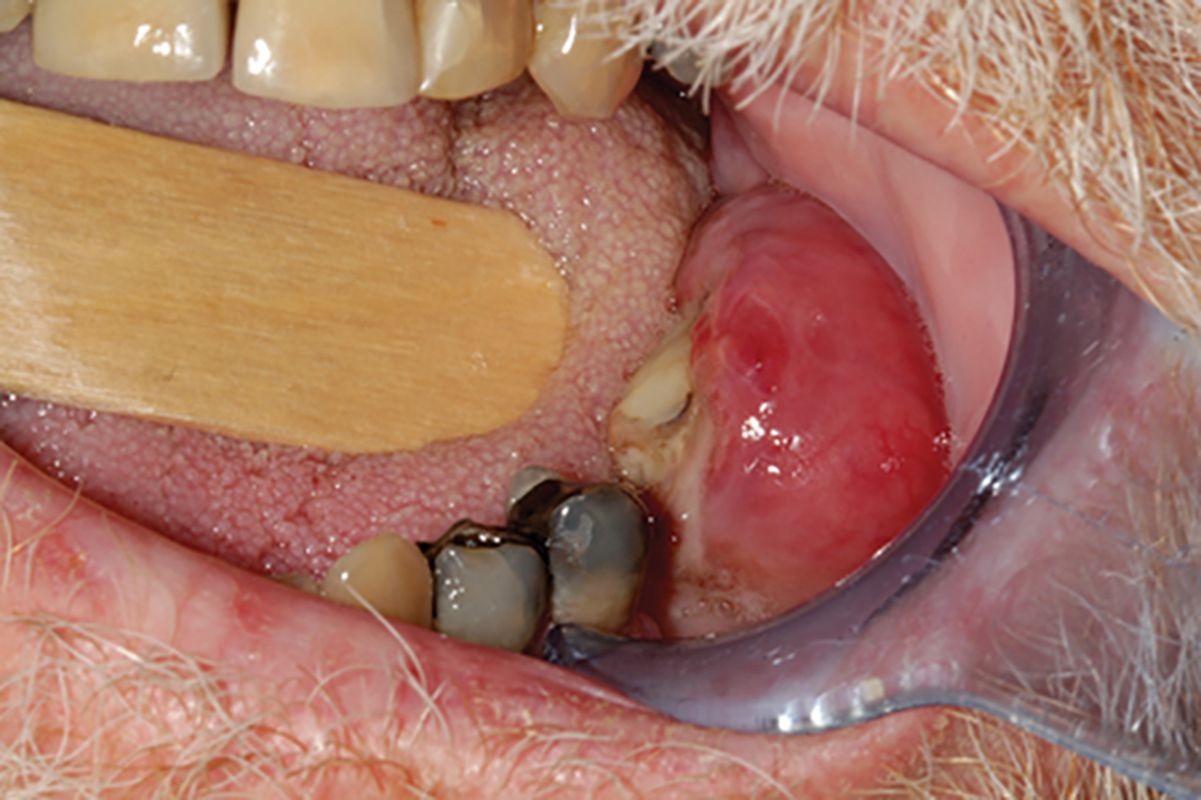

Ludwig’s Angina – A Case Report

Introduction Ludwig’s angina was first reported by Wilhelm Frederick von Ludwig in 1836. It is a severe and quickly spreading cellulitis characterized by significant involvement of the submandibular, sublingual and occasionally submental space. This condition is potentially fatal if not treated aggressively and promptly due to the cellulitis leading to airway compromise. 1,2 Prior to … Read more